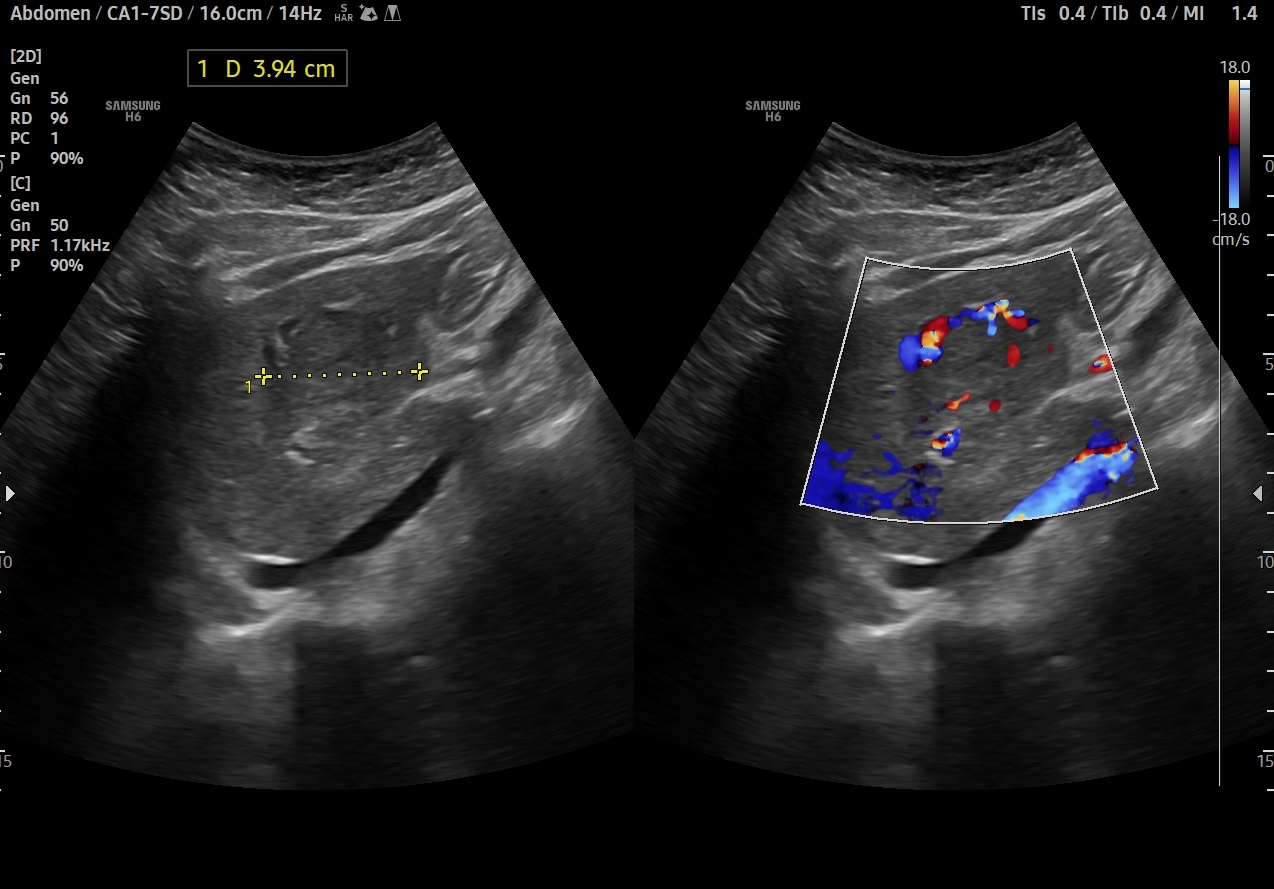

En el lóbulo hepático izquierdo visualizamos lesión focal iso-hipoecogénica respecto al parénquima hepático circundante que mide 4,6 x 4,5 x 3,9 cm y que presenta un aumento de la señal Doppler. Vemos la imagen tanto en cortes transversales como en cortes longitudinales, también con el modo Doppler activo. Resto de parénquima hepático y vía biliar de aspecto normal, sin otras alteraciones.